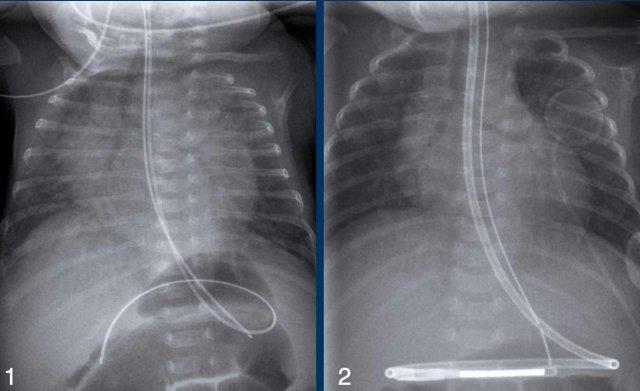

Trẻ sơ sinh, tuổi thai 27 tuần, được điều trị vì hội chứng suy hô hấp (RDS).

Lúc 2 ngày tuổi đột ngột có diễn biến xấu đi.

First study the images.

What are the findings?

Hình 1

Các đám mờ dạng lưới nốt hai bên phù hợp với hội chứng suy hô hấp cấp ở trẻ sơ sinh (IRDS), được điều trị bằng thở áp lực dương liên tục (CPAP).

Hình 2

Ở ngày tuổi thứ 2, phim X-quang cho thấy các vùng thấu quang tỏa ra ở phổi trái do khí thũng mô kẽ phổi (PIE).

Những hình ảnh này là của một trẻ sơ sinh tuổi thai 32 tuần, được điều trị vì Hội chứng suy hô hấp (RDS).

Một số biến chứng đã phát triển, bao gồm tràn khí màng phổi bên trái, đã được dẫn lưu.

Sau

khi dẫn lưu, tình trạng bệnh nhân xấu đi.

Phim X-quang cho thấy hình ảnh thấu quang dạng bong bóng tỏa ra hai bên do khí thũng mô kẽ phổi (PIE) hai bên.

Biểu hiện này rõ hơn ở bên trái.

Trong quá trình theo dõi, trẻ cũng phát triển tràn khí màng phổi bên phải.